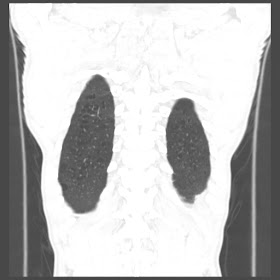

A 52 Years old man suffering with chest pain since 3 years

For seen patient record file please click here

HRCT Chest